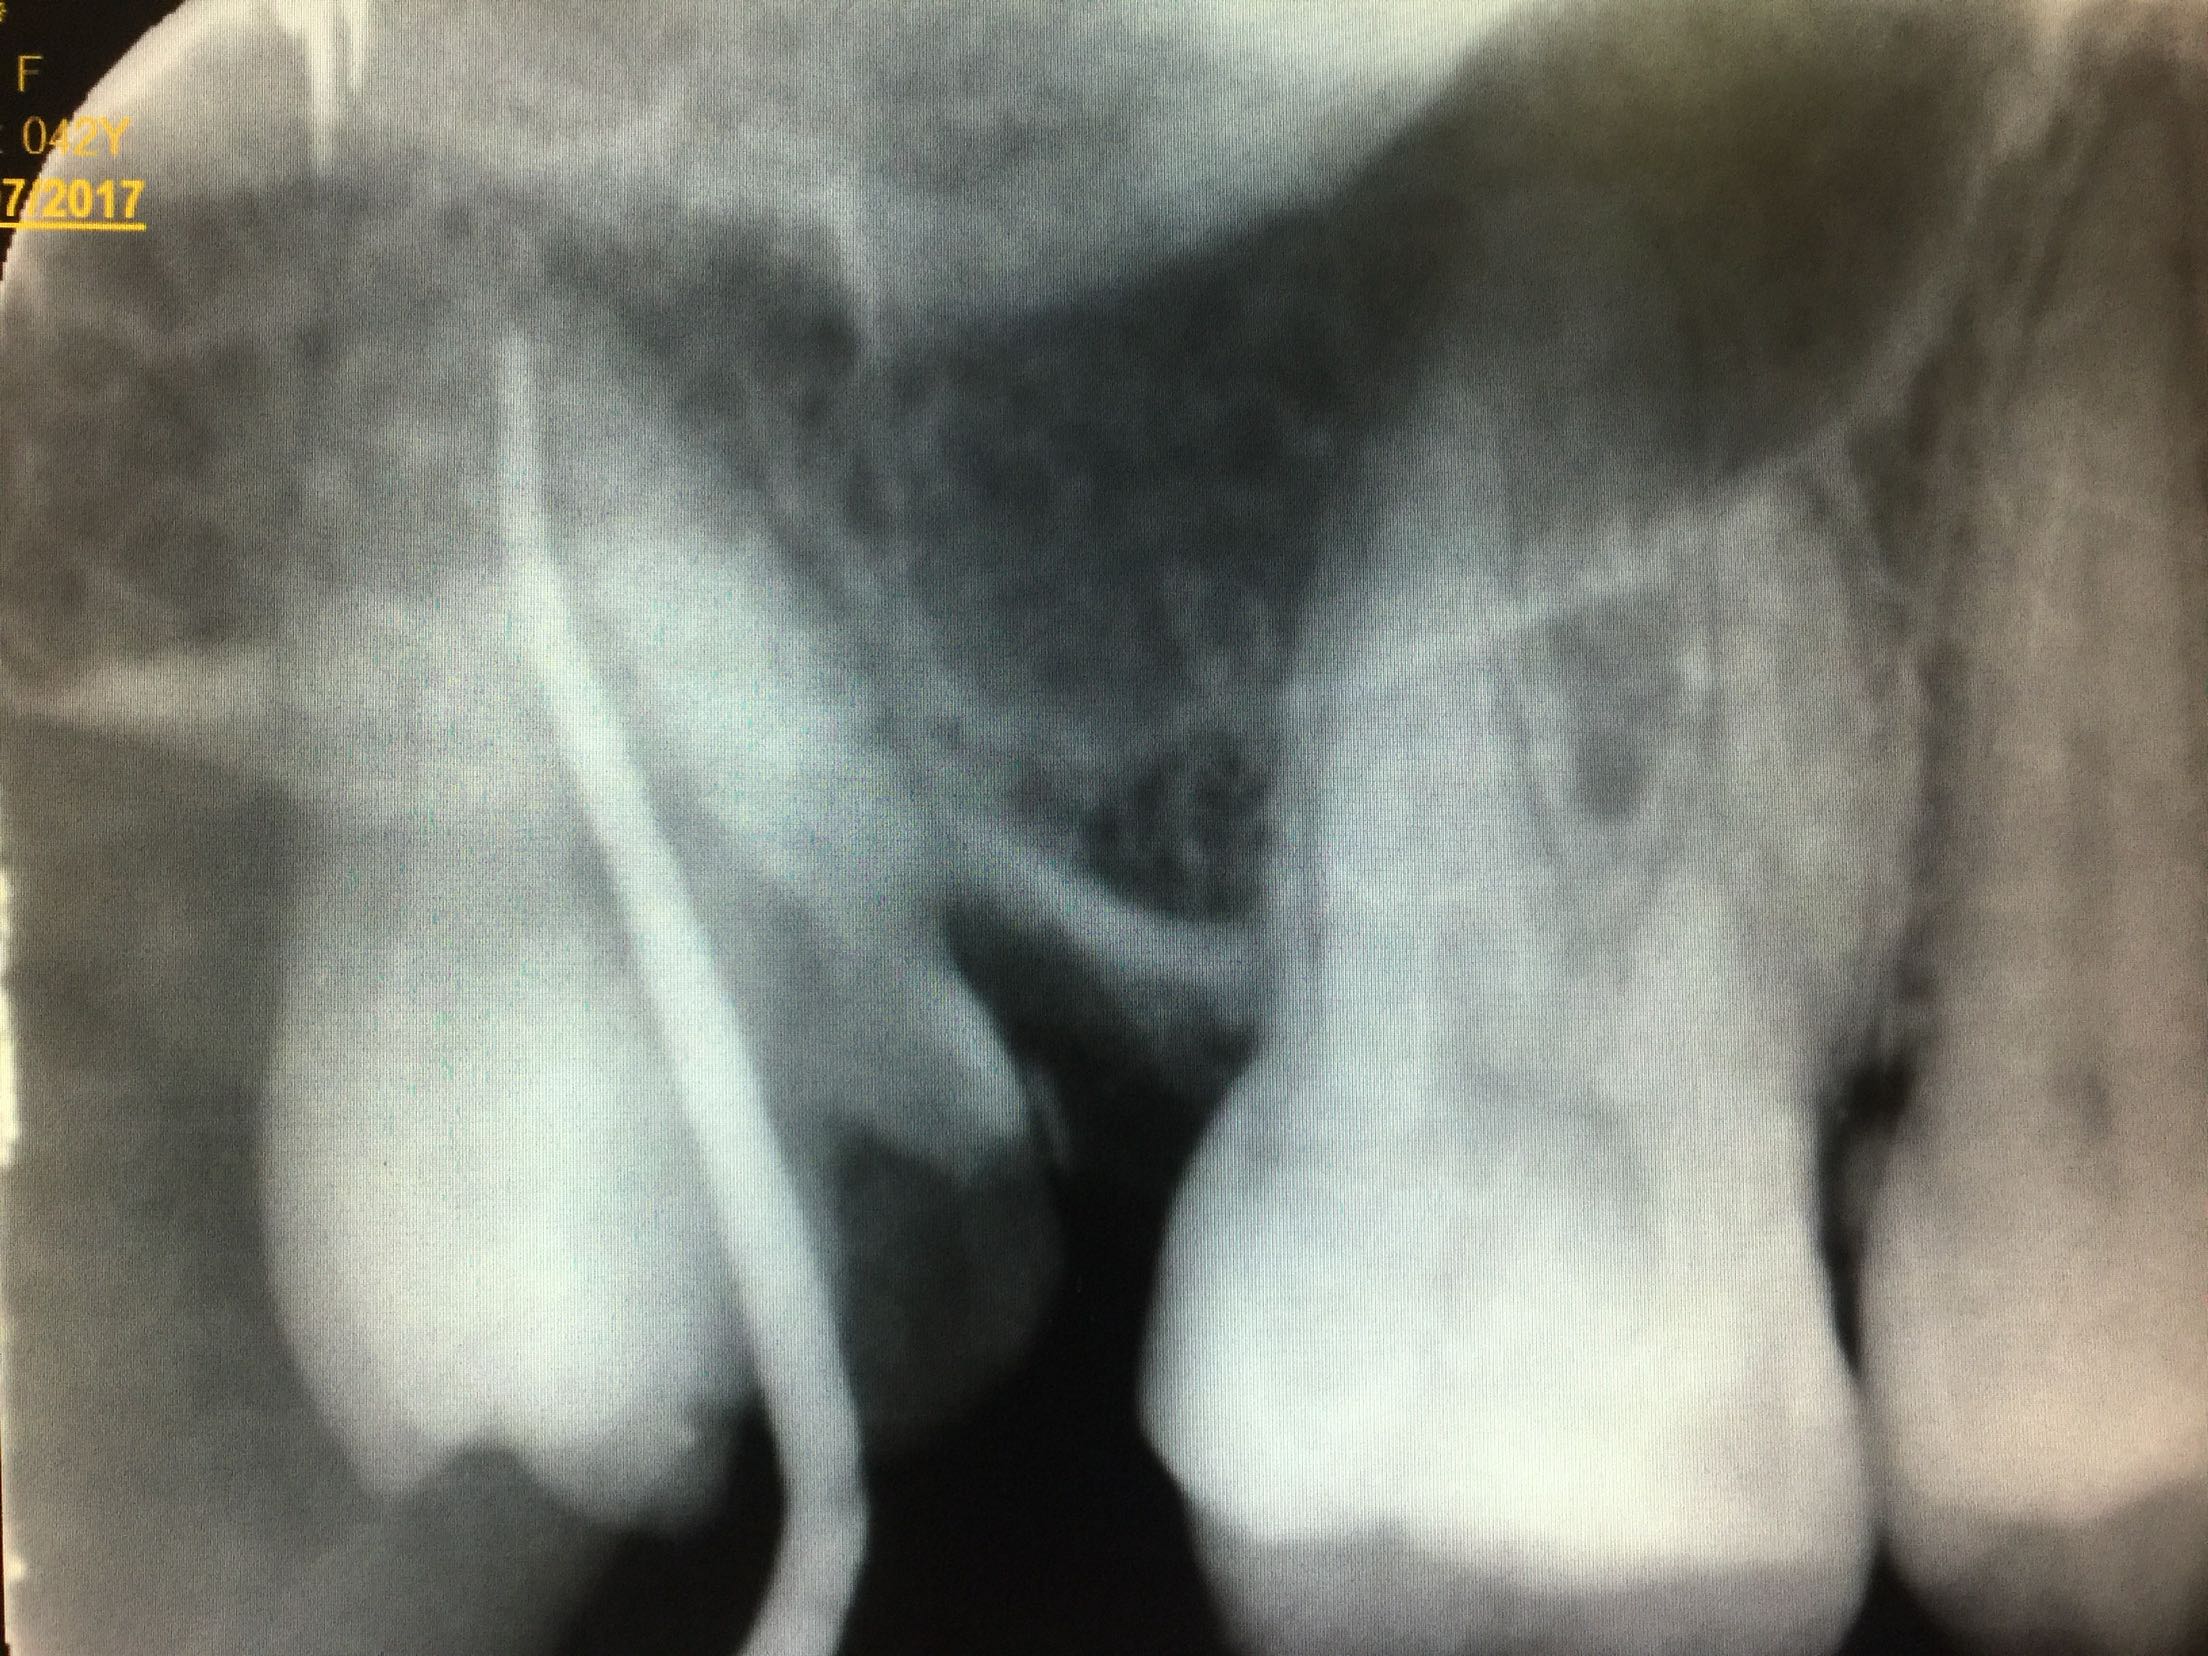

检查:全口卫生尚可,牙石+,软垢+,牙龈正常。18牙近中倾斜,近中邻合面龋,内有大量软龋,深达牙本质深层,已累及髓腔,冷+,探-,叩-,松-。颊侧牙龈未见异常。 17牙缺失,缺牙间隙小,无明显骨尖,对合牙无伸长。 X线:18牙近中邻合面可见龋坏,累及髓腔,未行根管治疗,根尖区未见暗影,牙槽骨吸收至颈部1/3。

诊断:18牙牙髓炎 17牙牙列缺损 治疗计划:因17牙缺牙间隙小,暂不行修复 18牙行去髓术 治疗:碧蓝麻局部浸润,18牙去净龋坏,开髓揭髓顶,探查根管1根,牙髓摘除术,k挫初步预备,根管测长仪测量根管长度,各根管内导入根管润滑剂EDTA,Protaper镊钛器械预备根管,冲洗,超声荡洗,水溶性氢氧化钙充填根管,暂封,约复诊。 一周后复诊 诊间无不适,18牙暂封完好,冷-,探-,叩-,松-。 试主尖,

大锥度牙胶尖+AH-PLUS糊剂充填根管,热压充填牙胶,暂封。树脂充填。